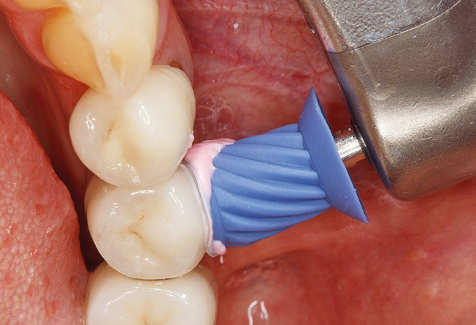

Unerlässlich für die UPT implantat prothetisch versorgter Patienten sind natürlich Arbeitsspitzen für die Reinigung von Implantatoberflächen. Der Implantatreinigungsaufsatz des hier verwendeten Systems zeichnet sich dabei durch eine spitz zulaufende sechskantige konische Form aus. Dieses Design erlaubt ein leichtes atraumatisches Eindringen in die periimplantäre Tasche und zeigt eine gute Reinigungsleistung (Abb. 7).

Nach der maschinellen Reinigung der Zahn und Implantatoberflächen erfolgt eine manuelle Instrumentierung der natürlichen Zahnoberflächen mit konventionellen Handinstrumenten. Bei der manuellen Reinigung ist insbesondere auf einen korrekten Anstellwinkel, eine ausreichende Schärfe, eine gute Abstützung und auf eine von apikal nach koronal gerichtete Arbeitsweise der Kürette zu achten. Zur Nachinstrumentierung der Implantatkonstruktionen sollten entweder Titan oder Carbonküretten verwendet werden (Abb. 8). Ergänzend zum Einsatz von Ultraschallgeräten können in der Erhaltungstherapie auch Pulverstrahlgeräte genutzt werden. Dabei ist jedoch zu berücksichtigen, dass diese Verfahren nicht zum Entfernen harter Beläge geeignet sind und daher die Verwendung von Hand oder Ultraschallinstrumenten nicht komplett ersetzen können. Abschließend erfolgt in jedem Fall eine mechanische Politur der zugänglichen Zahn und Implantatoberflächen mit Polierkelchen und Polierpasten (Abb. 9).